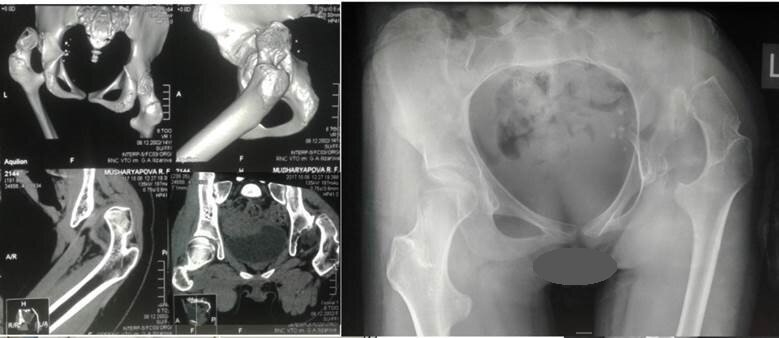

Рентгенография и КТ после операции: упор малого вертела в дно вертлужной впадины.